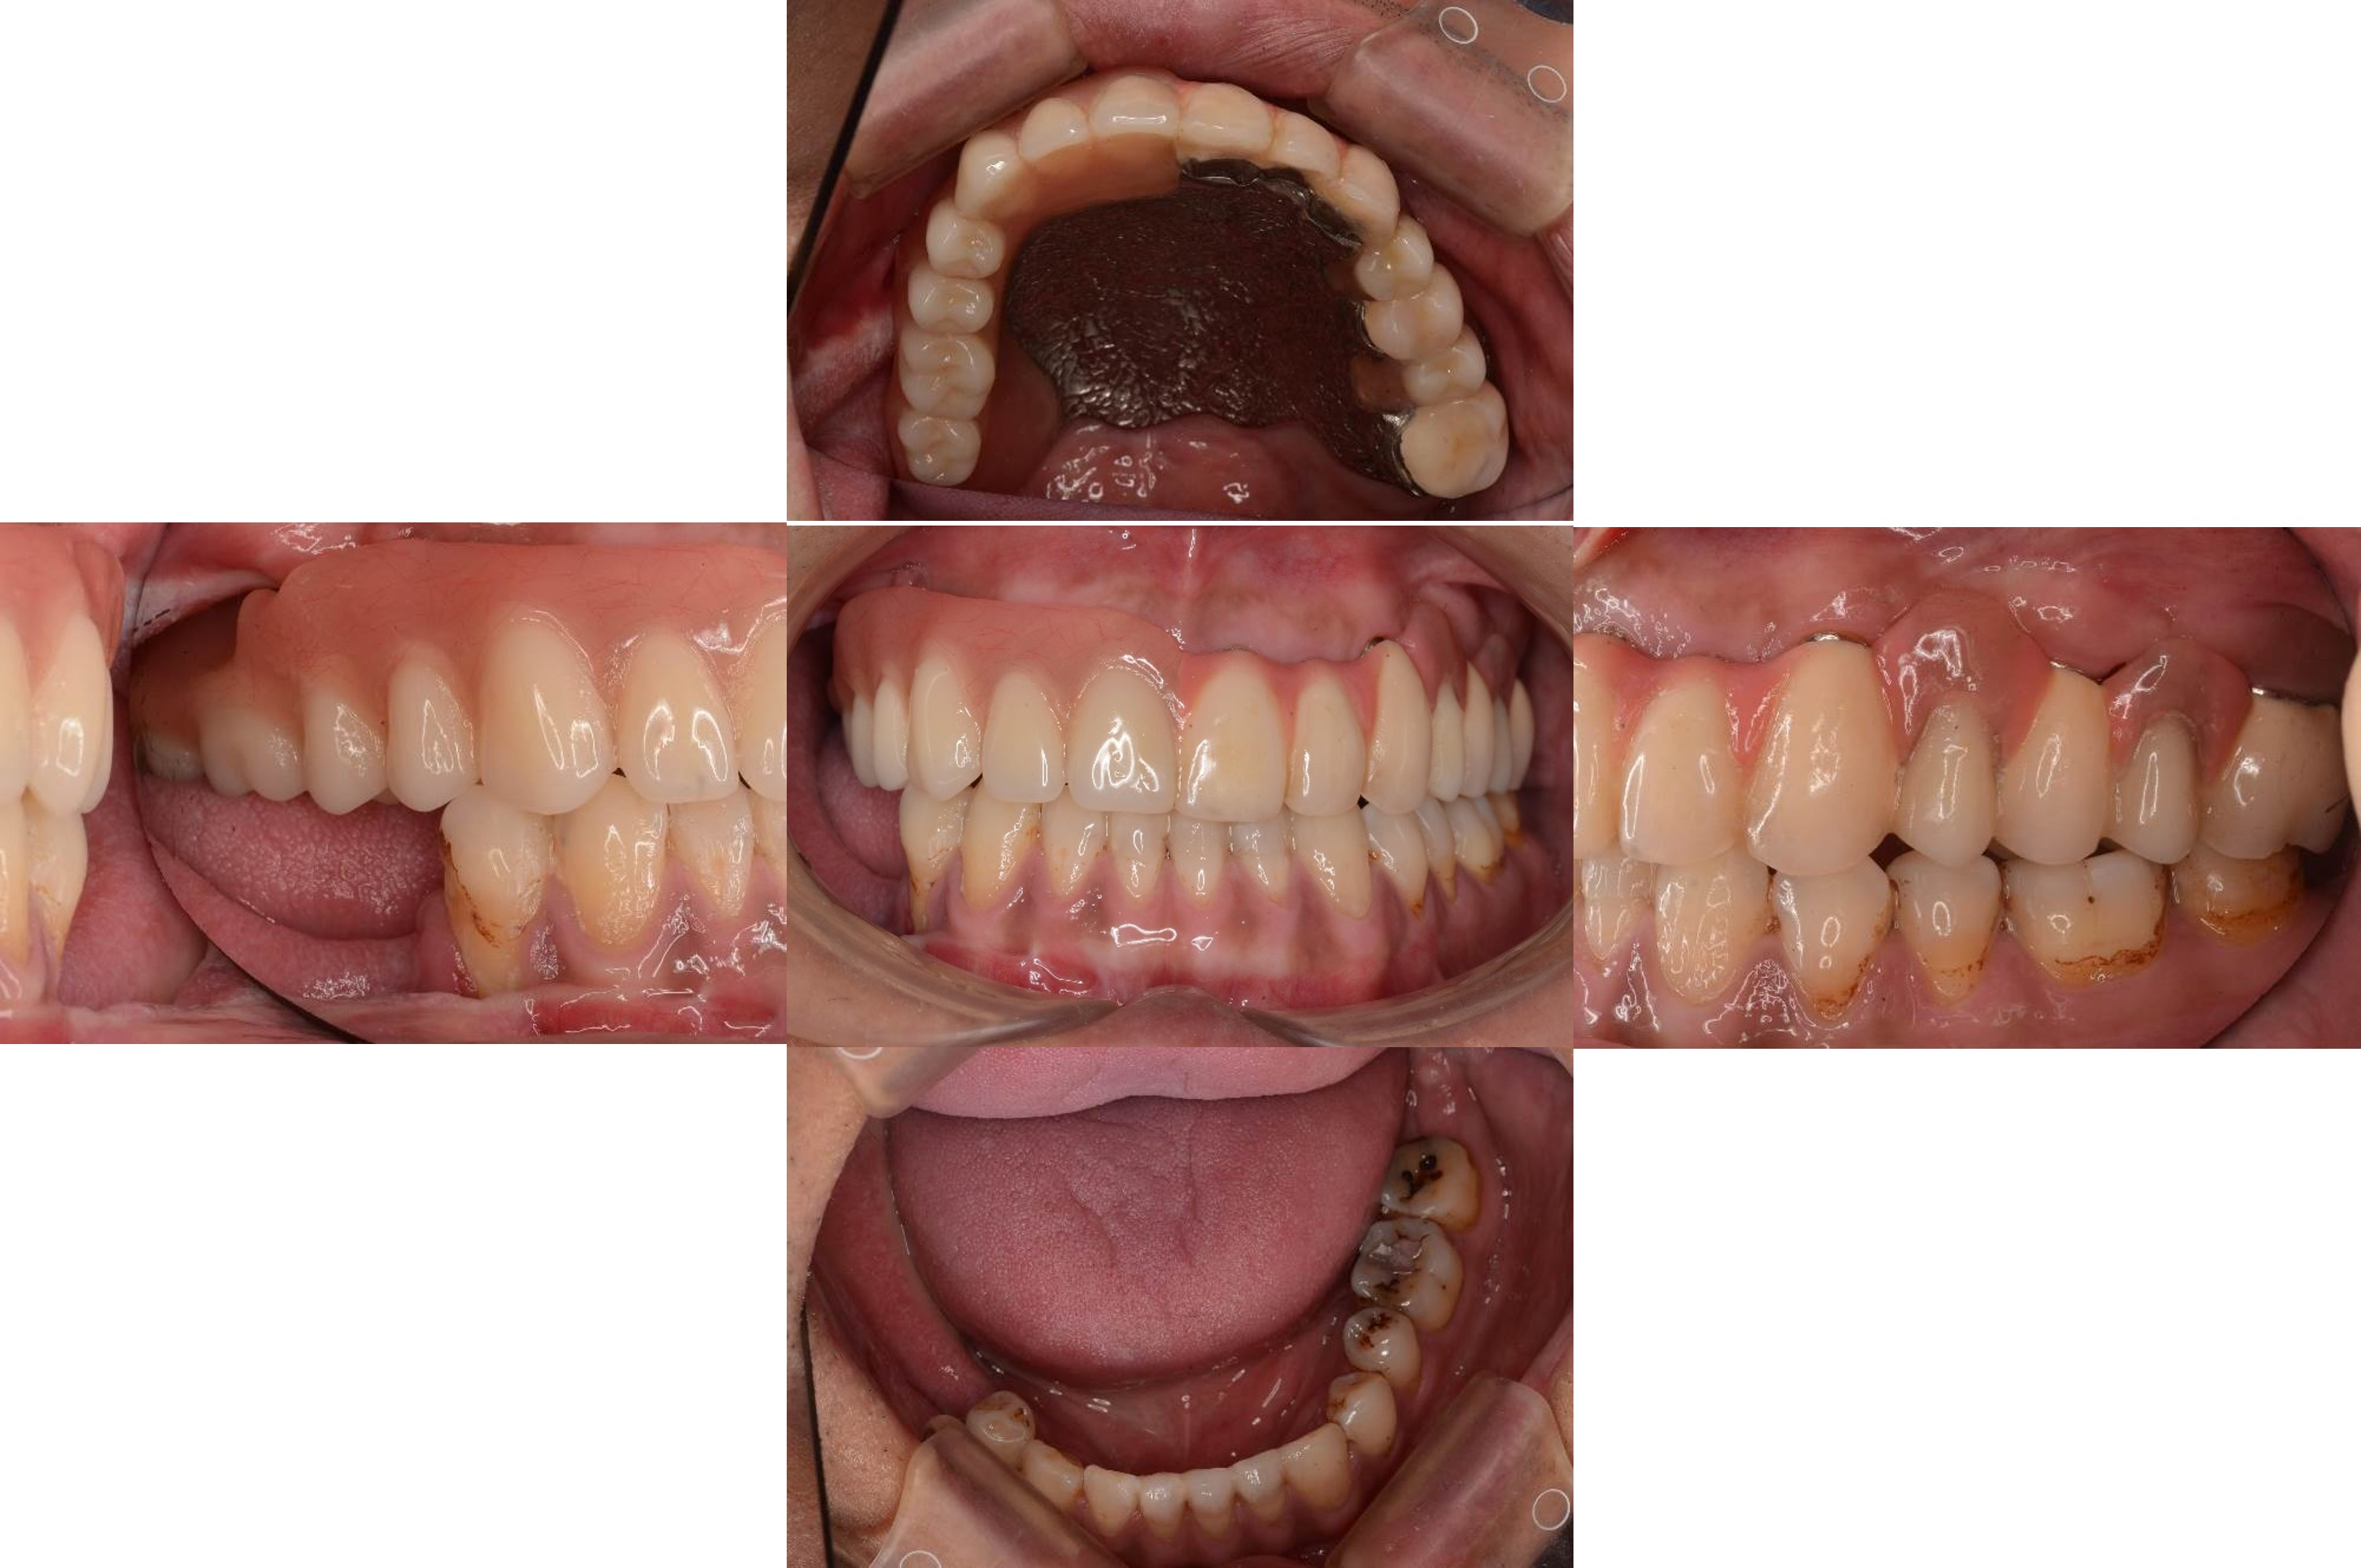

正式假牙完成

口內外冠與活動假牙定位

口內試戴

理想咬合支撐

口外支撐性良好

微笑時外形自然